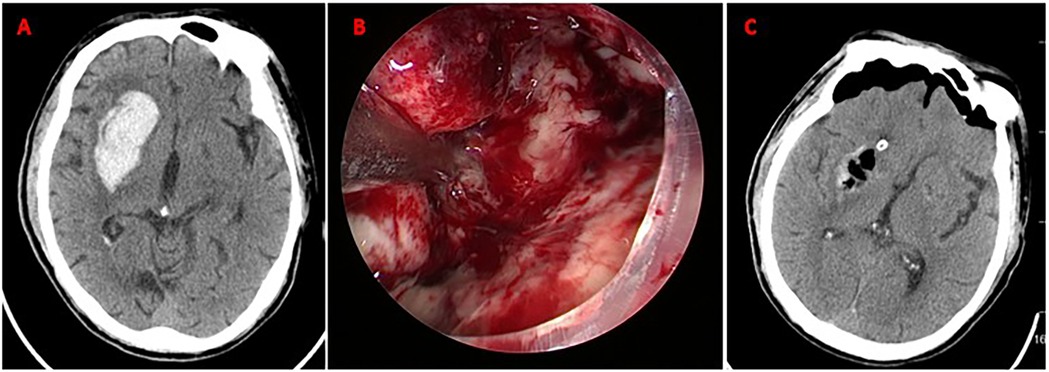

CT scans labeled A and C showing a brain with distinct areas of varying densities, likely indicating a pathology. Image B, centered, is an endoscopic view displaying a closer, detailed look at a lesion or area of interest, with visible red and white tissue.

Figure 3. Neuroendoscopic evacuation of right basal ganglia hematoma. (A) Axial CT demonstrates acute hypertensive hemorrhage (volume: 35 mL) in the right basal ganglia; (B) Intraoperative neuroendoscopic view during hematoma evacuation via a frontal approach. The hematoma cavity is visualized; (C) Postoperative axial CT scan confirming near-total hematoma evacuation (residual volume <2 mL). No new ischemic lesions or rebleeding are observed. Mild perihematomal edema is present.